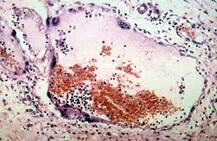

Nipah Virus

शरीर में 45 दिनों तक साइलेंटली रह सकता है निपाह वायरस, जानें कब हो जाता है खतरनाक?

निपाह वायरस के क्या हैं लक्षण, जानें बुखार और सिरदर्द हल्के में क्यों न लें?

कितना खतरनाक है निपाह वायरस, इसमें कब हो जाता है जान बचाना मुश्किल?

निपाह वायरस कितना खतरनाक, क्या है इससे बचने का तरीका?

केरल में निपाह वायरस का अलर्ट, जानें ये कितना खतरनाक और क्या होते हैं लक्षण

कितने दिन में ठीक हो जाता है निपाह वायरस का मरीज? जानें कैसे होता है इलाज